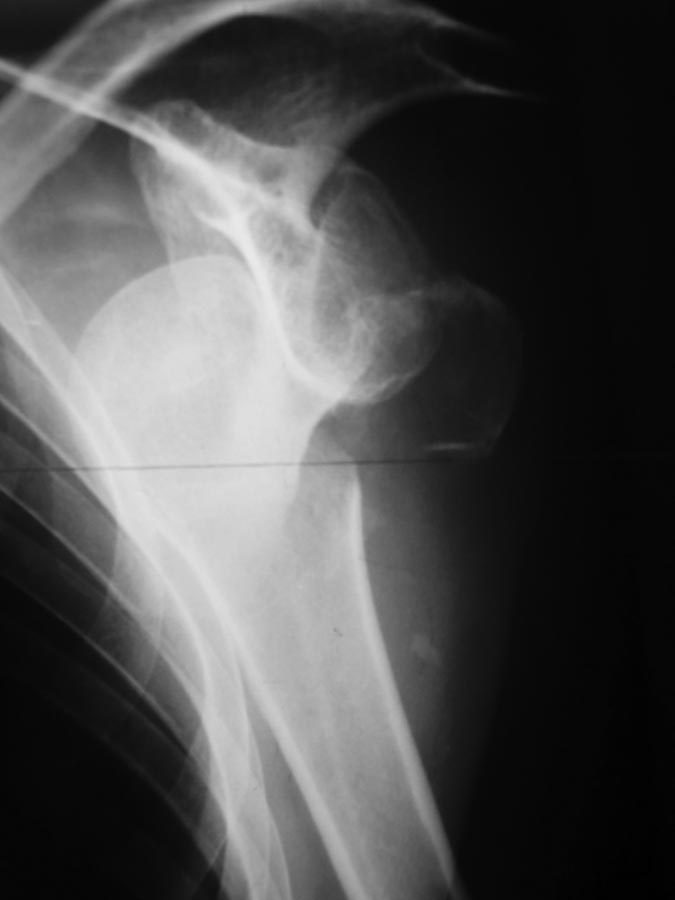

Застарелый вывих плеча с бугорком |

Уважаемые форумчане! Хотелось бы услышать мнение по поводу лечения. 05.12.16 поступил пациент 46 лет с неизвестной давностью травмы плечевого сустава, предположительно до 10 суток.

К этому времени дважды лечился в отделении наркологии с алкогольным делирием. На следующий день после поступления к нам диагносцирована абсцедирующая пневмония, предположительно аспирационная. 08.12.16 производилась попытка закрытого вправления под общим обезболиванием - без результата. На 20.12.6 антибиотикотерапия завершена. При осмотре обращает на себя внимание обширное кровоизлияние на половине грудной клетки со стороны пораженной конечности. Развилась контрактура в локтевом суставе. Думаю об открытом вправлении и фиксации бугорка, возможно сделать дупликатуру капсулы, либо оставить как есть с дальнейшей разработкой у врачей ЛФК. Интересует ваше мнение, коллеги.